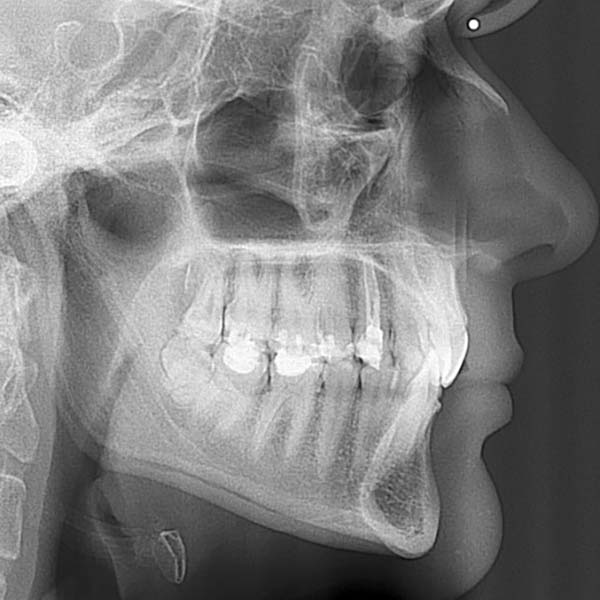

BEFORE

This lady visited me complaining that her upper teeth cover the lower ones excessively.

Examination revealed a severe deep bite, covering almost all parts of the lower teeth, in addition to a severe backward tilt in her upper front teeth, which affected the beauty of her smile.

Fortunately, this woman did not suffer from problems in her joint before the date of her visit to the clinic, Since these cases usually persist for a long time, causing pain and problems in the joint, (due to the patient’s need to open his mouth widely, each time he wants to free his lower jaw from the upper teeth)